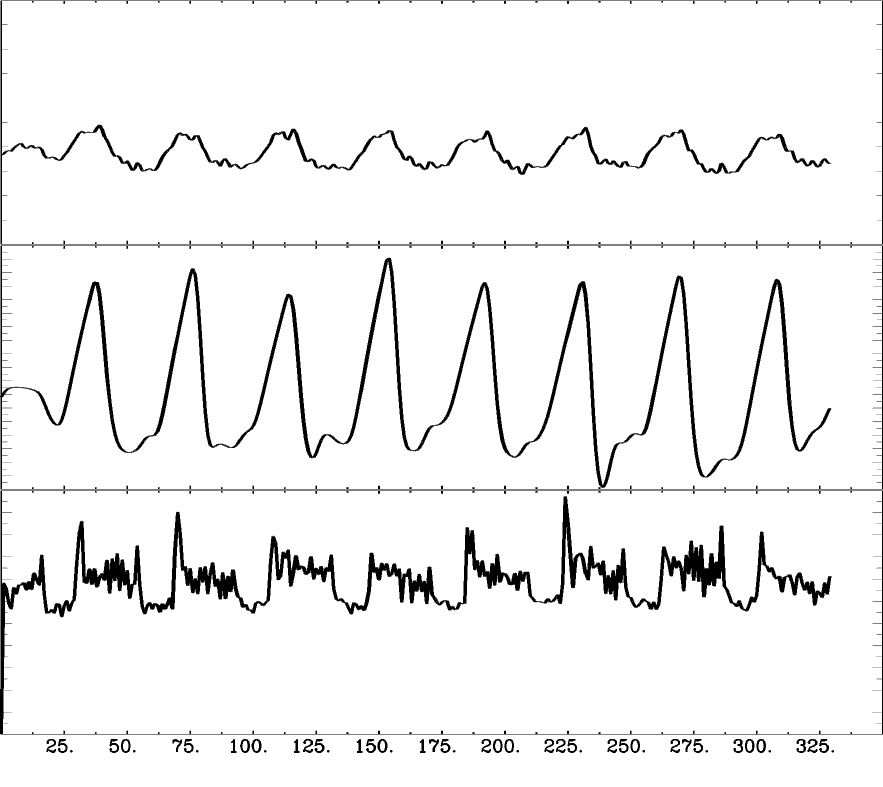

Methods: Analysis

- Peaks detection in exhaled CO2 traces

- Amplitude envelope (PETCO2) convolved with HRF

- Find max correlation of PETCO2 and average GM

- PETCO2 signal shifted between -9 and +9 sec

- Shifted regressors interpolated at the TR

- Compute GLM with each lagged regressor and nuisance regression (12 motion parameters and low frequency trends)

- For each voxel, select the lagged model with highest explained variance (R²)

For comparison:

- Computed non-optimised CVR map (measurement delay)

- Computed GLM with each regressor, without motion parameters

- Computed GLM with each regressor, after motion was regressed out

↓

optimised CVR map and lag map

Methods: preprocessing

Functional:

- motion realignment

- skullstripping

- optimal combination (OC)

- distortion correction

CO2 traces:

- (supervised) peak detection

- linear interpolation of peaks and convolution with HRF

- cross-correlation with average GM signal

- creation of lagged regression (range: ±9 s, step: 0.3 s)

- interpolation to fMRI TR